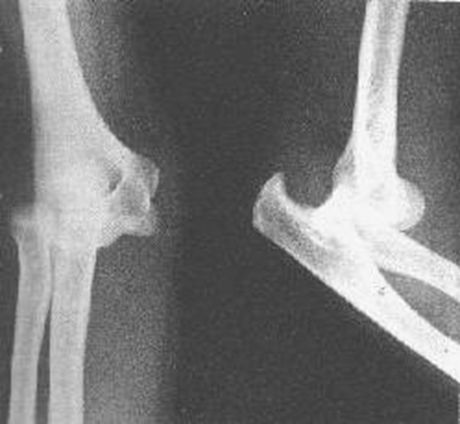

肱骨髁上骨折

肱骨髁间骨折

桡骨头骨折